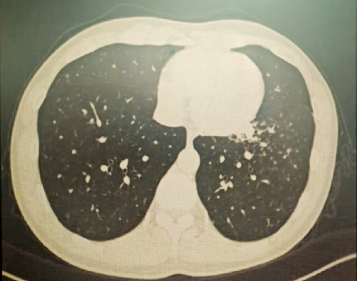

以上是他的胸部CT影像,主要表现为左下肺炎症,片絮影+磨玻璃影。

明确诊断后我们给予了正规治疗,患者咳嗽症状迅速缓解,1月后复查胸部CT提示肺部病变大部分吸收。

肺部感染的影像学特征

多发性结节伴快速进展

CT表现为双肺多发实性结节(直径0.5-3cm),结节边缘可见毛刺征及分叶征,特征性表现为短期内体积呈几何级数增长(如1周内增大10倍),需与转移瘤、结核球等鉴别。

混合性密度影与胸腔积液

40%病例出现磨玻璃影与实变影共存,部分结节中央可见液化坏死;30%伴单侧渗出性胸腔积液,积液分析呈渗出性但培养阴性,此表现易误诊为脓胸。